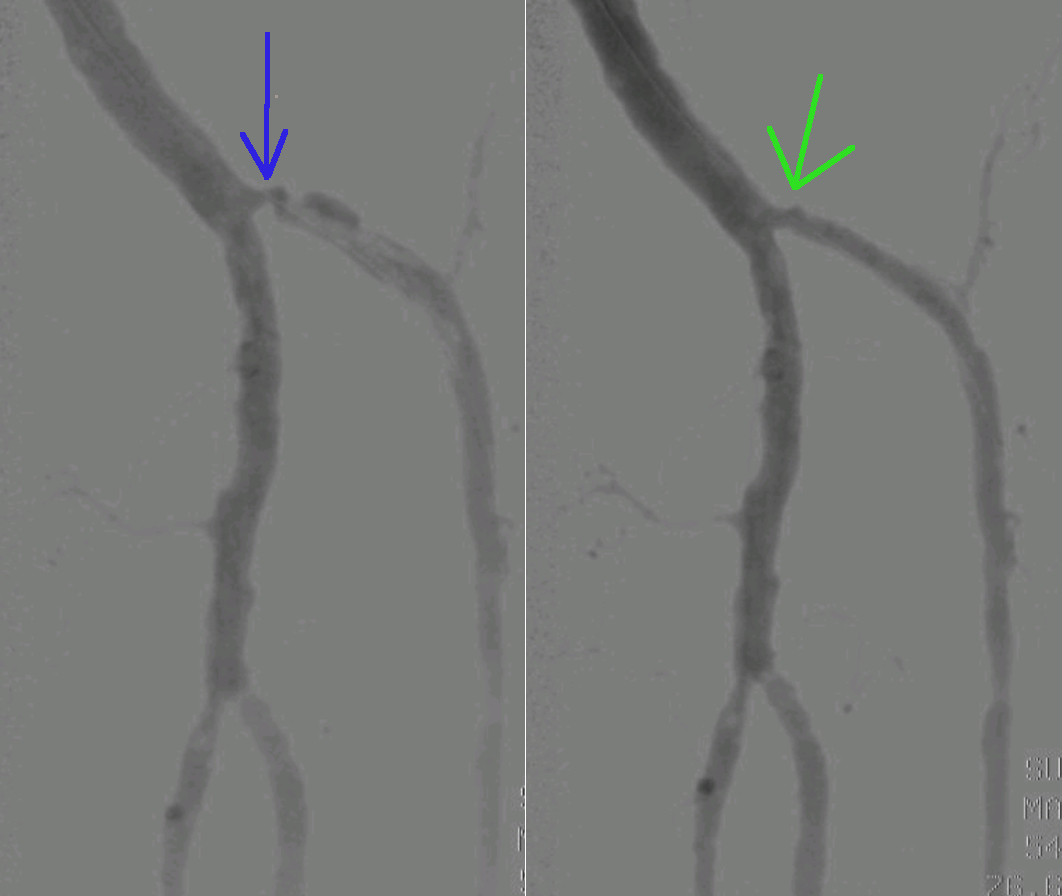

Levo je stanje pred PTA posegom (modra puščica). Žile je zožena, kar zmanjšuje dotok krvi v nogo. Na sliki desno je stanje po PTA posegu (zelena puščica). Žila je razširjena in noga dobi dovolj krvi.

Dober rezultat PTA posega. Ponovno je vzpostaljena dobra prekrvavitev na nogi. Preprečen je amputacijski poseg. Noga je ohranjena.